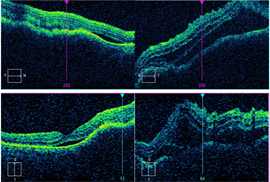

The patient presented with new worsening vision in both eyes. Around one month prior to presentation, he was switched to immunotherapy with ipilimumab, nivolumab, and cabozantinib. Visual acuity measured count fingers in both eyes from a previous 20/80 in the right eye (OD) and 20/200 in the left eye (OS). Intraocular pressure, pupillary exam, and confrontational visual fields were normal. Anterior segment examination was overall unremarkable with clear corneas and trace nuclear sclerotic cataracts bilaterally. Dilated fundoscopic exam showed new mild bilateral vitritis and stable bilateral choroidal lesions with overlying pigmentary changes (Figure 1). Greater subretinal fluid was present in the macula than previously observed. Optical coherence tomography confirmed increased subretinal fluid and revealed a subretinal fibrinoid response (Figure 2).

Figure 1. Color fundus photos showing bilateral choroidal lesions with overlying pigment changes. |

Figure 2. Spectral-domain optical coherence tomography (SD-OCT) demonstrating intraretinal fluid, and subretinal fluid with subretinal fibrinoid response bilaterally. |